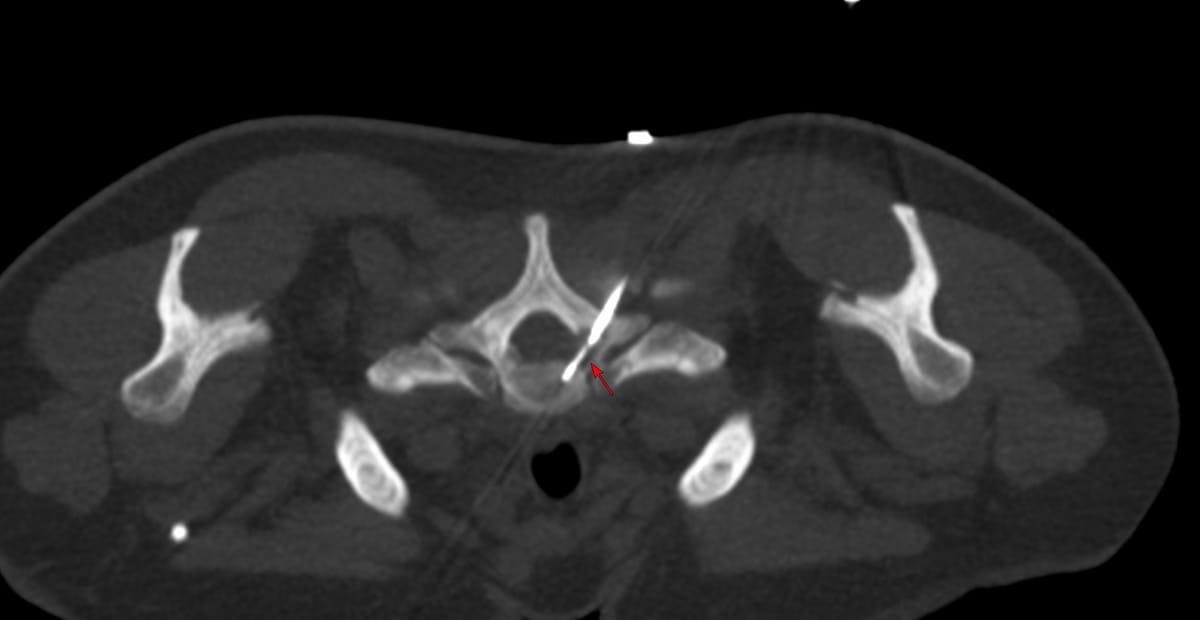

Case of the Day 100 - 2025 09 10 - T2 Dark Thoracic Spinal Vertebral Lesion - Transpedicular Biopsy

Dorsal spine lesions can be easily biopsied using transpedicular, costovertebral and perivertebral approaches.